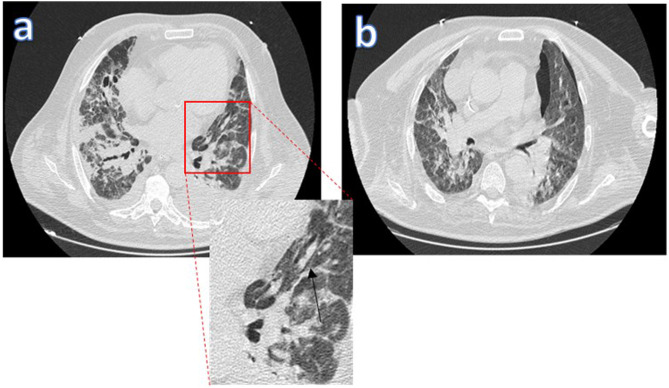

Figura 2.

Efecto Macklin en paciente COVID-19 con SDRA en VMI. La ventana pulmonar de la TC torácica (a) muestra una colección lineal de aire contigua a la vaina broncoavascular del lóbulo superior izquierdo (la flecha negra indica el efecto Macklin). b) Aparición de neumotórax días después.